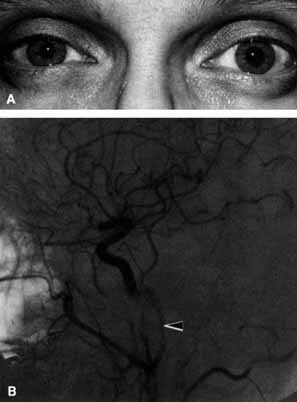

A 70-year-old woman presented with a 6-month history of progressive diplopia and ptosis. She demonstrated complete right third, fourth, and sixth cranial nerve palsies, and hypesthesia of cranial nerve V1 (Fig. 22A). The right pupil was dilated. Computed tomography (CT) disclosed an intracavernous aneurysm (see Fig. 22B).

Fig. 22 A. A 70-year-old woman with complete right third, fourth, and sixth cranial nerve palsies. Hypesthesia of cranial nerve V1 was also present. B. CT scan demonstrates an intracavernous aneurysm (arrow).

The so-called superior orbital fissure syndrome occurs when an infiltrative, inflammatory, or ischemic event occurs within the superior orbital fissure, but not in the orbital apex.4 A complete superior orbital fissure syndrome occurs when all the neurovascular components passing through the superior orbital fissure are damaged, producing a total ophthalmoplegia, ptosis, and anesthesia of cranial nerve V1 (see Fig. 22A). The pupil may be dilated, miotic, or midposition and fixed, depending on the balance of parasympathetic and sympathetic damage. The superior ophthalmic vein, best seen on CT, may be dilated if venous outflow from the orbit is obstructed. Clues to venous outflow obstruction are increased intraocular pressure, fullness of the upper eyelid, and hyperemia of the deep Tenon's vessels. Ophthalmoscopically, the retinal veins may be dilated. The effect of a lesion in the superior orbital fissure or the anterior cavernous sinus cannot be differentiated clinically (see Fig. 22B). When the posterior cavernous sinus becomes involved, hypesthesia of cranial nerve V2 may also be present.

The only difference between a superior orbital fissure syndrome and an orbital apex syndrome is the presence of visual loss caused by optic nerve involvement. Visual acuity, color vision, or the visual field are abnormal. An ipsilateral relative afferent pupil defect is present.